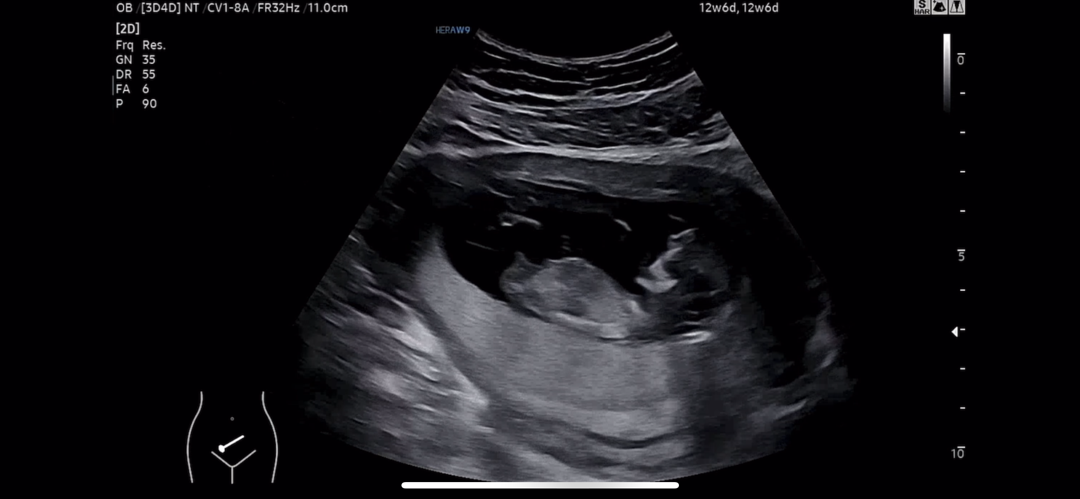

성별예측할수있응까요?

각도법 저는 도저히 어찌보는지 모르겠어서요ㅠ

아들 같아요!! ㅎㅎ

아들 같으시네요 ㅎㅎ

아들 같네요~

아들 같아요 ㅎㅎ